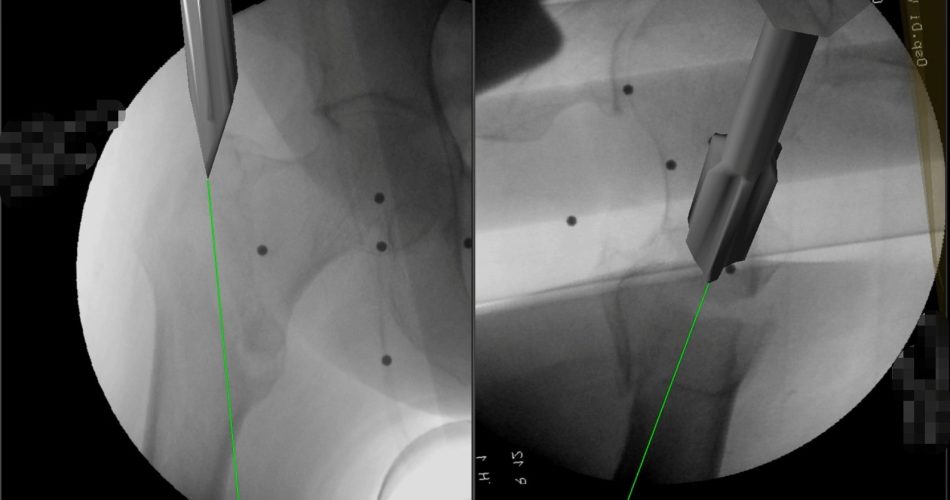

foto intraoperatoria realtà virtuale (4)

Trattare la frattura del femore utilizzando la realtà virtuale, preziosa “alleata” degli occhi e delle mani del chirurgo ortopedico. L’Ortopedia e Traumatologia dell’Ospedale “Di Venere” di Bari, con le prime 20 operazioni già eseguite con questo sistema tecnologico, ha varcato la nuova frontiera dell’innovazione applicata ad uno degli interventi preso a modello da Agenas per misurare la qualità e l’efficacia del sistema sanitario: la riduzione della frattura del collo del femore. La novità è racchiusa nell’acronimo EBANAV (Endovis Bio Advanced NAVigator), un sistema di navigazione virtuale che permette ai chirurghi ortopedici di visualizzare il campo operatorio in tre dimensioni e a 360 gradi, con notevoli vantaggi in termini di precisione millimetrica e quindi di azzeramento dei margini d’errore, riduzione delle radiazioni ionizzanti, oltre a tempi d’intervento – circa 25 minuti – ridotti e resi omogenei rispetto alle tecniche tradizionali.

Grazie ad una unità di elaborazione e visualizzazione computerizzata e al posizionamento – assolutamente non invasivo – di un sistema di sensori al paziente, all’amplificatore di brillanza (l’apparecchiatura radiologica che permette di visualizzare l’arto su cui intervenire) e allo strumentario, l’ambiente operatorio viene trasposto dal mondo reale a quello virtuale. «L’ortopedico – spiega il dr. Caiaffa – in sostanza può operare guardando un monitor sul quale vengono riprodotte immagini in continuo e in tre dimensioni dell’articolazione, evitando i macchinosi passaggi da un’immagine fissa all’altra della tecnica tradizionale».

Ridurre la frattura e stabilizzarla con il chiodo diventa così un’operazione più semplice, in cui i “limiti” umani dell’operatore vengono superati dalla navigazione virtuale, capace di guidare l’atto chirurgico con la  riproduzione in 3D, estremamente precisa, del posizionamento del mezzo di sintesi. La realtà virtuale, in tal modo, permette di vedere in ogni momento dove è collocato il nostro sistema nello spazio e rispetto alla frattura del paziente, oltre che consentire un’alta predittività delle misure dell’impianto.